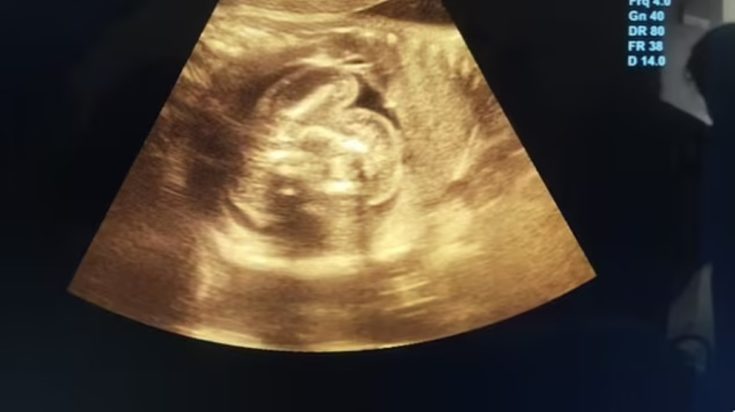

Ένα σπάνιο ιατρικό φαινόμενο συνέβη σε μία γυναίκα στην Ινδία, όταν ανακαλύφθηκε ότι το αγέννητο μωρό της είχε δύο άλλα αναπτυσσόμενα έμβρυα μέσα στο σώμα του. Η 32χρονη επισκέφθηκε το νοσοκομείο για έναν υπέρηχο ρουτίνας, ενώ ήταν έγκυος 35 εβδομάδων.

Αν και οι προηγούμενοι υπέρηχοί της ήταν φυσιολογικοί, οι γιατροί εντόπισαν «μία επιπλέον δομή που περιείχε οστά» στην κοιλιά του αγέννητου αγοριού της. Στη συνέχεια, η περαιτέρω εξέταση αποκάλυψε δύο εμβρυϊκές μορφές μέσα στην κοιλιά του μωρού.

Ο γιατρός Prasad Agarwal, ο οποίος πραγματοποίησε τον υπέρηχο, δήλωσε: «Ήμουν τυχερός για να παρατηρήσω κάτι εξαιρετικά ασυνήθιστο με αυτό το μωρό, ένα φυσιολογικά αναπτυσσόμενο έμβρυο με μερικά οστά και μια δομή που έμοιαζε με έμβρυο στην κοιλιά του».

«Σκέφτηκα ότι αυτό δεν είναι φυσιολογικό. Ήταν μια περίπτωση “έμβρυο εντός εμβρύου”, μία από τις σπανιότερες περιπτώσεις στον κόσμο», πρόσθεσε.